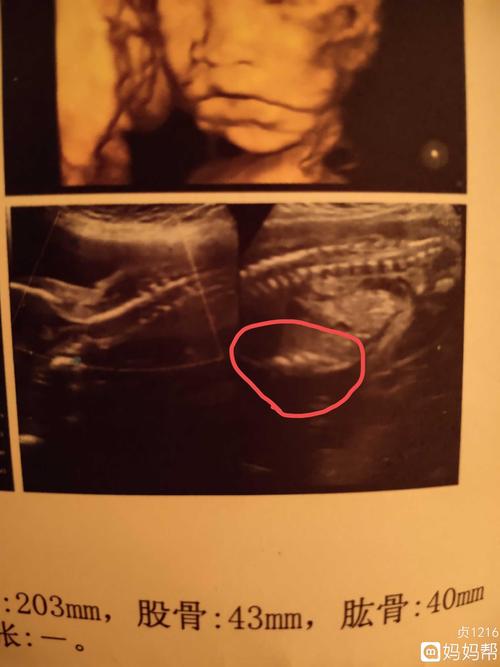

女孩四维彩超图及数据根据四维彩超的数据怎么区分男孩女孩